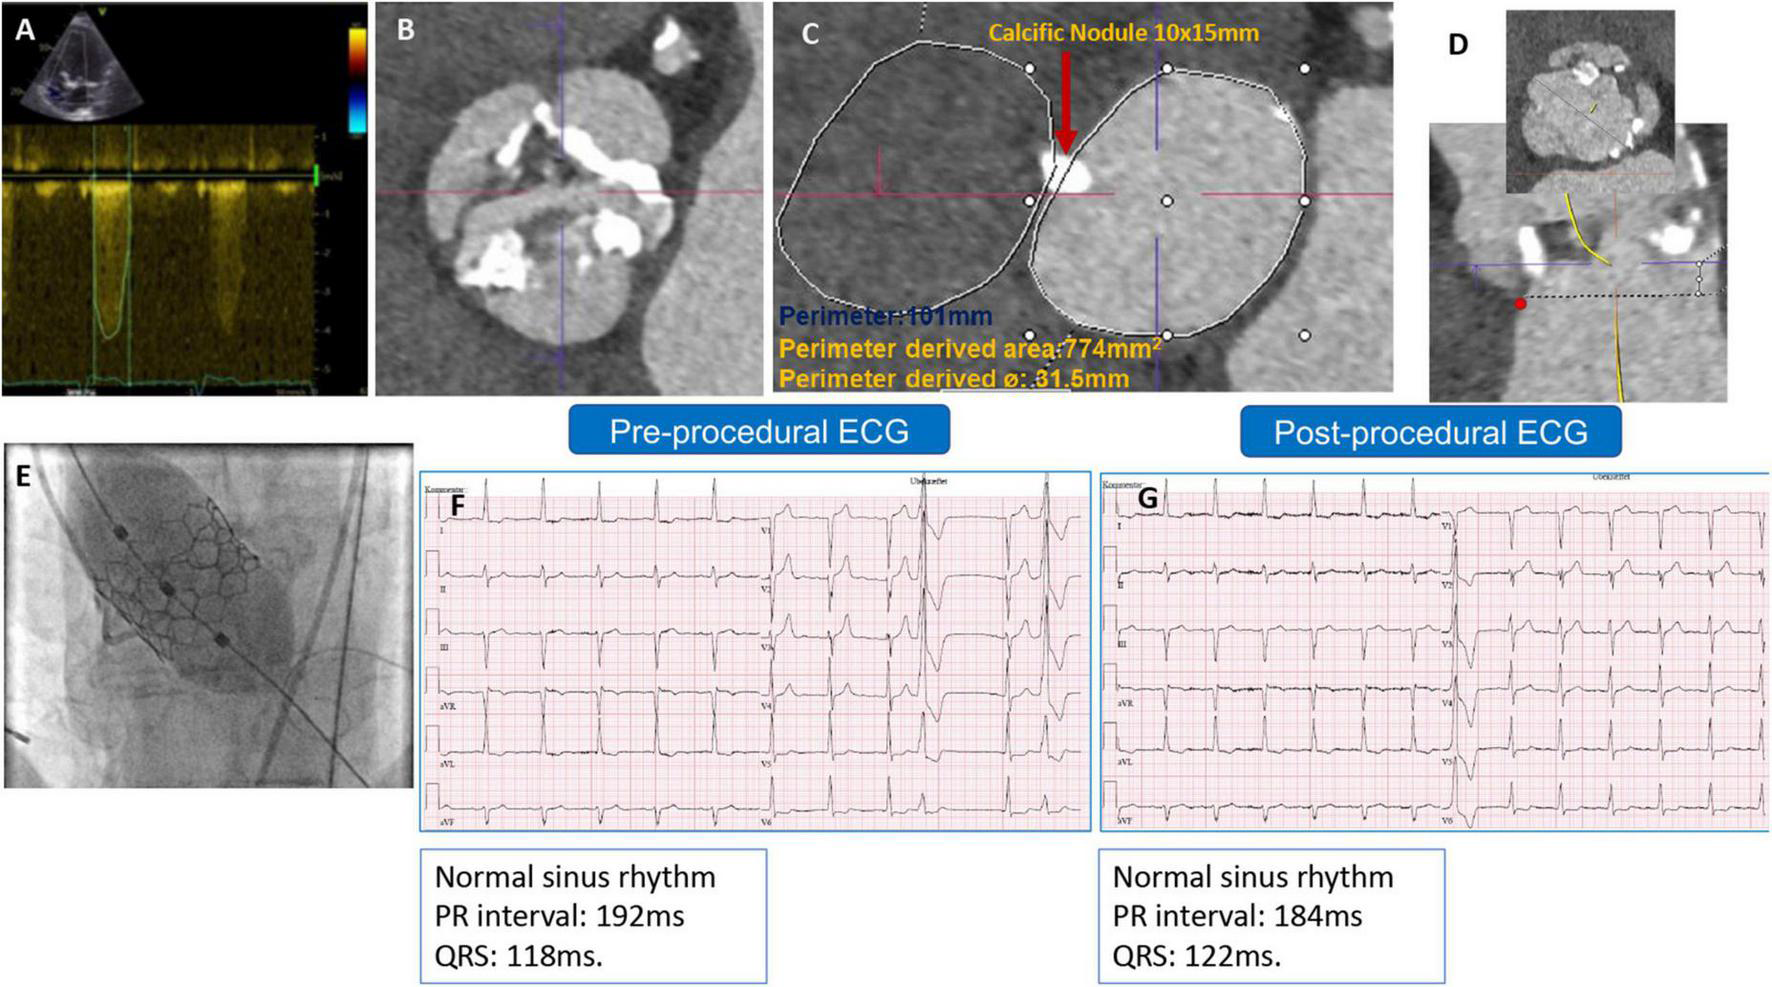

The second patient was a 79-year-old man with severe AS. A TTE revealed a maximum and mean PG of 71 and 54 mmHg, respectively, an EOA of 0.7 cm2, and a preserved LV-EF. A preprocedural-CCTA showed a calcified BAV Sievers type 1-a, with a large annular calcific nodule (10 × 15 mm). The measurements documented a large annulus with a perimeter of 101 mm, a perimeter-derived diameter of 31.5 mm, an area of 774 mm2, an ICD of 35 mm, and wide sinuses (Figure 2). A 32 mm Myval-XL was selected for TF-TAVR with the risk of annular injury due to the annular calcium chunk (not extending to the LVOT). Balloon pre-dilatation was performed using a Sapien-25 mm balloon. The device deployment was performed using the Navigator delivery system in the tri-coplanar view (RAO4/CRA5) with pacing over the LV guidewire. Final aortography (Supplementary Video 2) and invasive transvalvular gradient revealed Sellers’ grade 0 and 5 mmHg. The post-procedural ECG showed no alteration of the conduction (Figures 2F,G). The patient had an uneventful in-hospital course and was discharged on day 2 with antiplatelet monotherapy (Aspirin). The patient’s 30-day outcomes were uneventful (Table 1).

FIGURE 2

(A) Preprocedural AV continuous wave Doppler with high maximum velocity, (B) preprocedural MSCT showing BAV with partially fused L-R raphe and significant AV calcifications, (C) annulus measurement showing large annulus with large annular calcific nodule, (D) LVOT profile view (no calcification) and ICD 4–5 mm above the annulus = 35 mm, (E) Myval-XL 32 mm deployment, (F) preprocedural ECG, and (G) postprocedural ECG without changes.